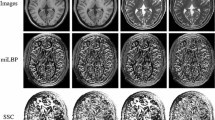

The paper addresses the problem and proposes a simple, compact, fast and generally applicable modality-independent binary gradient angle descriptor (BGA) based on the rationale of gradient orientation alignment. The BGA can be easily calculated at each voxel by coding the quadrant in which a local gradient vector falls, and it has an extremely low computational complexity, requiring only three convolutions, two multiplication operations and two comparison operations. Meanwhile, the binarized encoding of the gradient orientation makes the BGA more resistant to image degradations compared with conventional gradient orientation methods. The BGA can extract similar feature descriptors for different modalities and enable the use of simple similarity measures, which makes it applicable within a wide range of optimization frameworks.

The results for pairwise multimodal and monomodal registrations between various images (T1, T2, PD, T1c, Flair) consistently show that the BGA significantly outperforms localized mutual information. The experimental results also confirm that the BGA can be a reliable alternative to the sum of absolute difference in monomodal image registration. The BGA can also achieve an accuracy of \(1.41\pm 1.1~\hbox {mm}\), similar to that of the SSC, for the deformable registration of inhale and exhale CT scans. Specifically, for the highly challenging deformable registration of preoperative MRI and 3D intraoperative ultrasound images, the BGA achieves a similar registration accuracy of \(2.33\pm 1.2~\hbox {mm}\) compared with state-of-the-art approaches, with a computation time of 18.3 s per case.

Jiang D, Shi Y, Yao D, Wang M, Song Z (2016) miLBP: a robust and fast modality-independent 3D LBP for multimodal deformable registration. Int J Comput Assist Radiol 11:997–1005